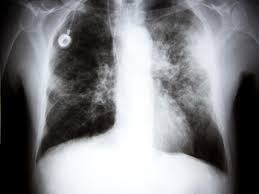

Missed Lung Lesions Side By Side Comparison Of Chest Radiography With Mdct Springerlink from media.springernature.com Taking a sample of the nodule with a needle or surgery. Actively scan device characteristics for identification. Have no signs or symptoms of lung cancer. The scan only takes a few minutes and is not painful. When you need them—and when you don't. Performing a chest radiograph is one of the first investigative steps if a person reports symptoms that may be suggestive of lung cancer. A local anaesthetic is used to numb the skin. Learn who should take the test and who should not.

Performing a chest radiograph is one of the first investigative steps if a person reports symptoms that may be suggestive of lung cancer. Taking a sample of the nodule with a needle or surgery. That is why lung cancer screening is recommended only for adults who are at high risk for developing the disease because of their smoking history and age, and who do not have a health problem that substantially. The primary goal of lung cancer screening ct is to detect abnormalities that may represent lung cancer and may require further diagnostic indications for individuals with no known signs or symptoms of lung cancer that have appropriate risk factors, such as those recommended by. It is used to look for early signs of lung cancer.

Ct scans to find lung cancer in smokers. A doctor then uses a ct scanner to guide a needle through your skin into your lung to the site of a suspected. Currently, lung cancer is one of the deadly diseases in the world. Ct scans expose you to radiation, which has been linked to cancer. ■ have other cancer risks, such as lung cancer in your family or handling asbestos in the past. Lung cancer is one of the most common and serious types of cancer. Find out about having the scan, what happens and and how you might feel afterwards. Performing a chest radiograph is one of the first investigative steps if a person reports symptoms that may be suggestive of lung cancer. Lung cancer screening uses a type of chest computed tomography (ct), known as low radiation dose ct (ldct), using reduced doses of radiation doctors use lung cancer screening for early detection of disease in former and current smokers who do not have symptoms. Radiological scan is useful in detecting early npc. The scan only takes a few minutes and is not painful. If you do have these symptoms, see your doctor. Another name for ldct is.